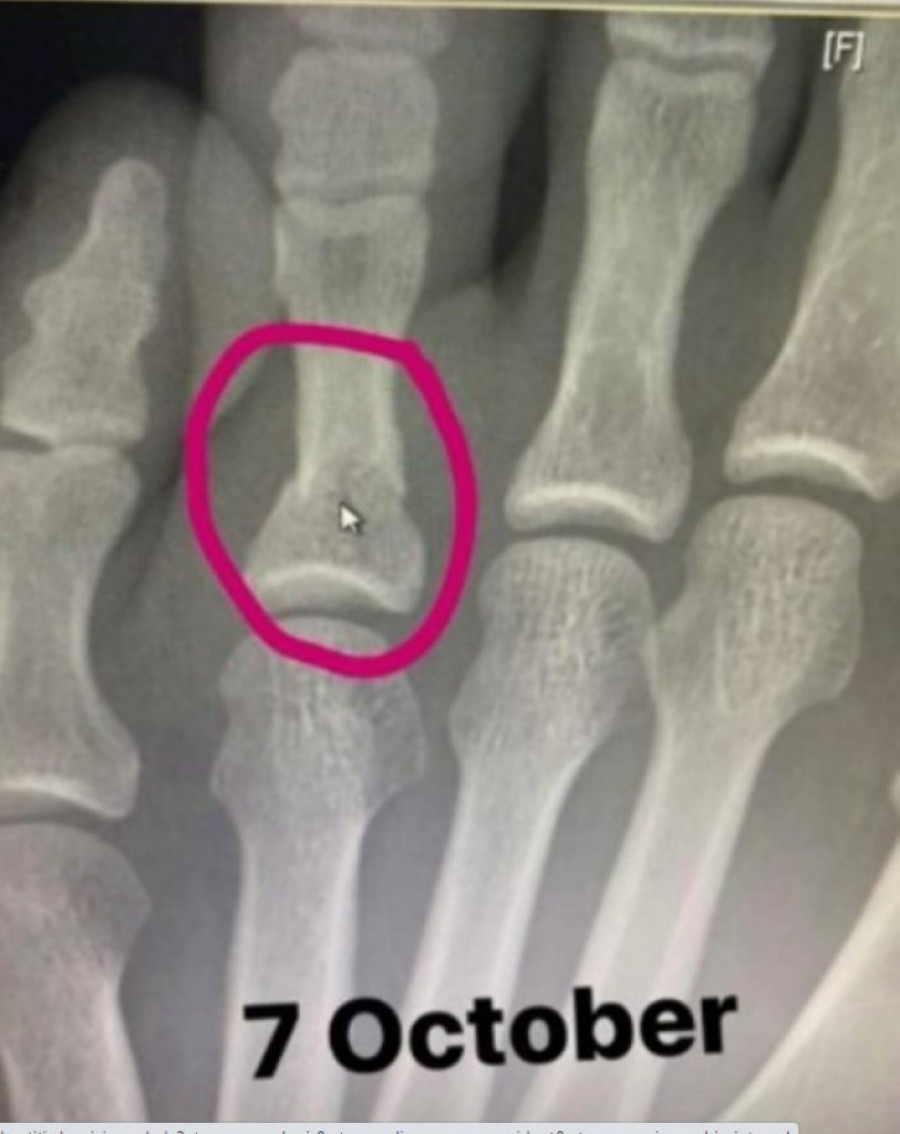

Foto: www.profimedia.rsNaime, prvi čovek UDC Dejna Vajt otkrio je da se neporaženi MMA prvak u Abu Dabiju borio uprkos tome što je imao slomljeno stopalo i prst, a sam Habib je priču potkrepio rendgenskim snimcima i to od 7. oktobra, dakle samo dve sedmice pre meča!